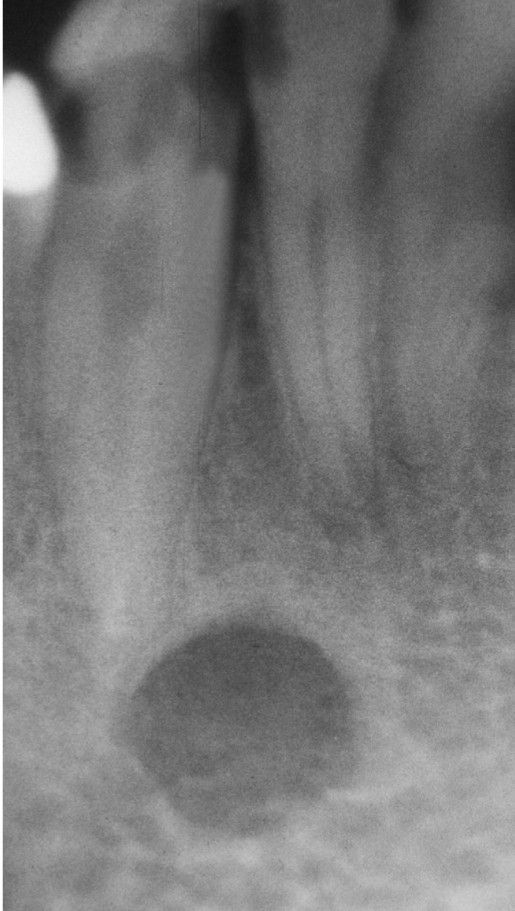

Stafne defect

Anterior radiolucent lesion of the body of the mandible associated with the sublingual gland